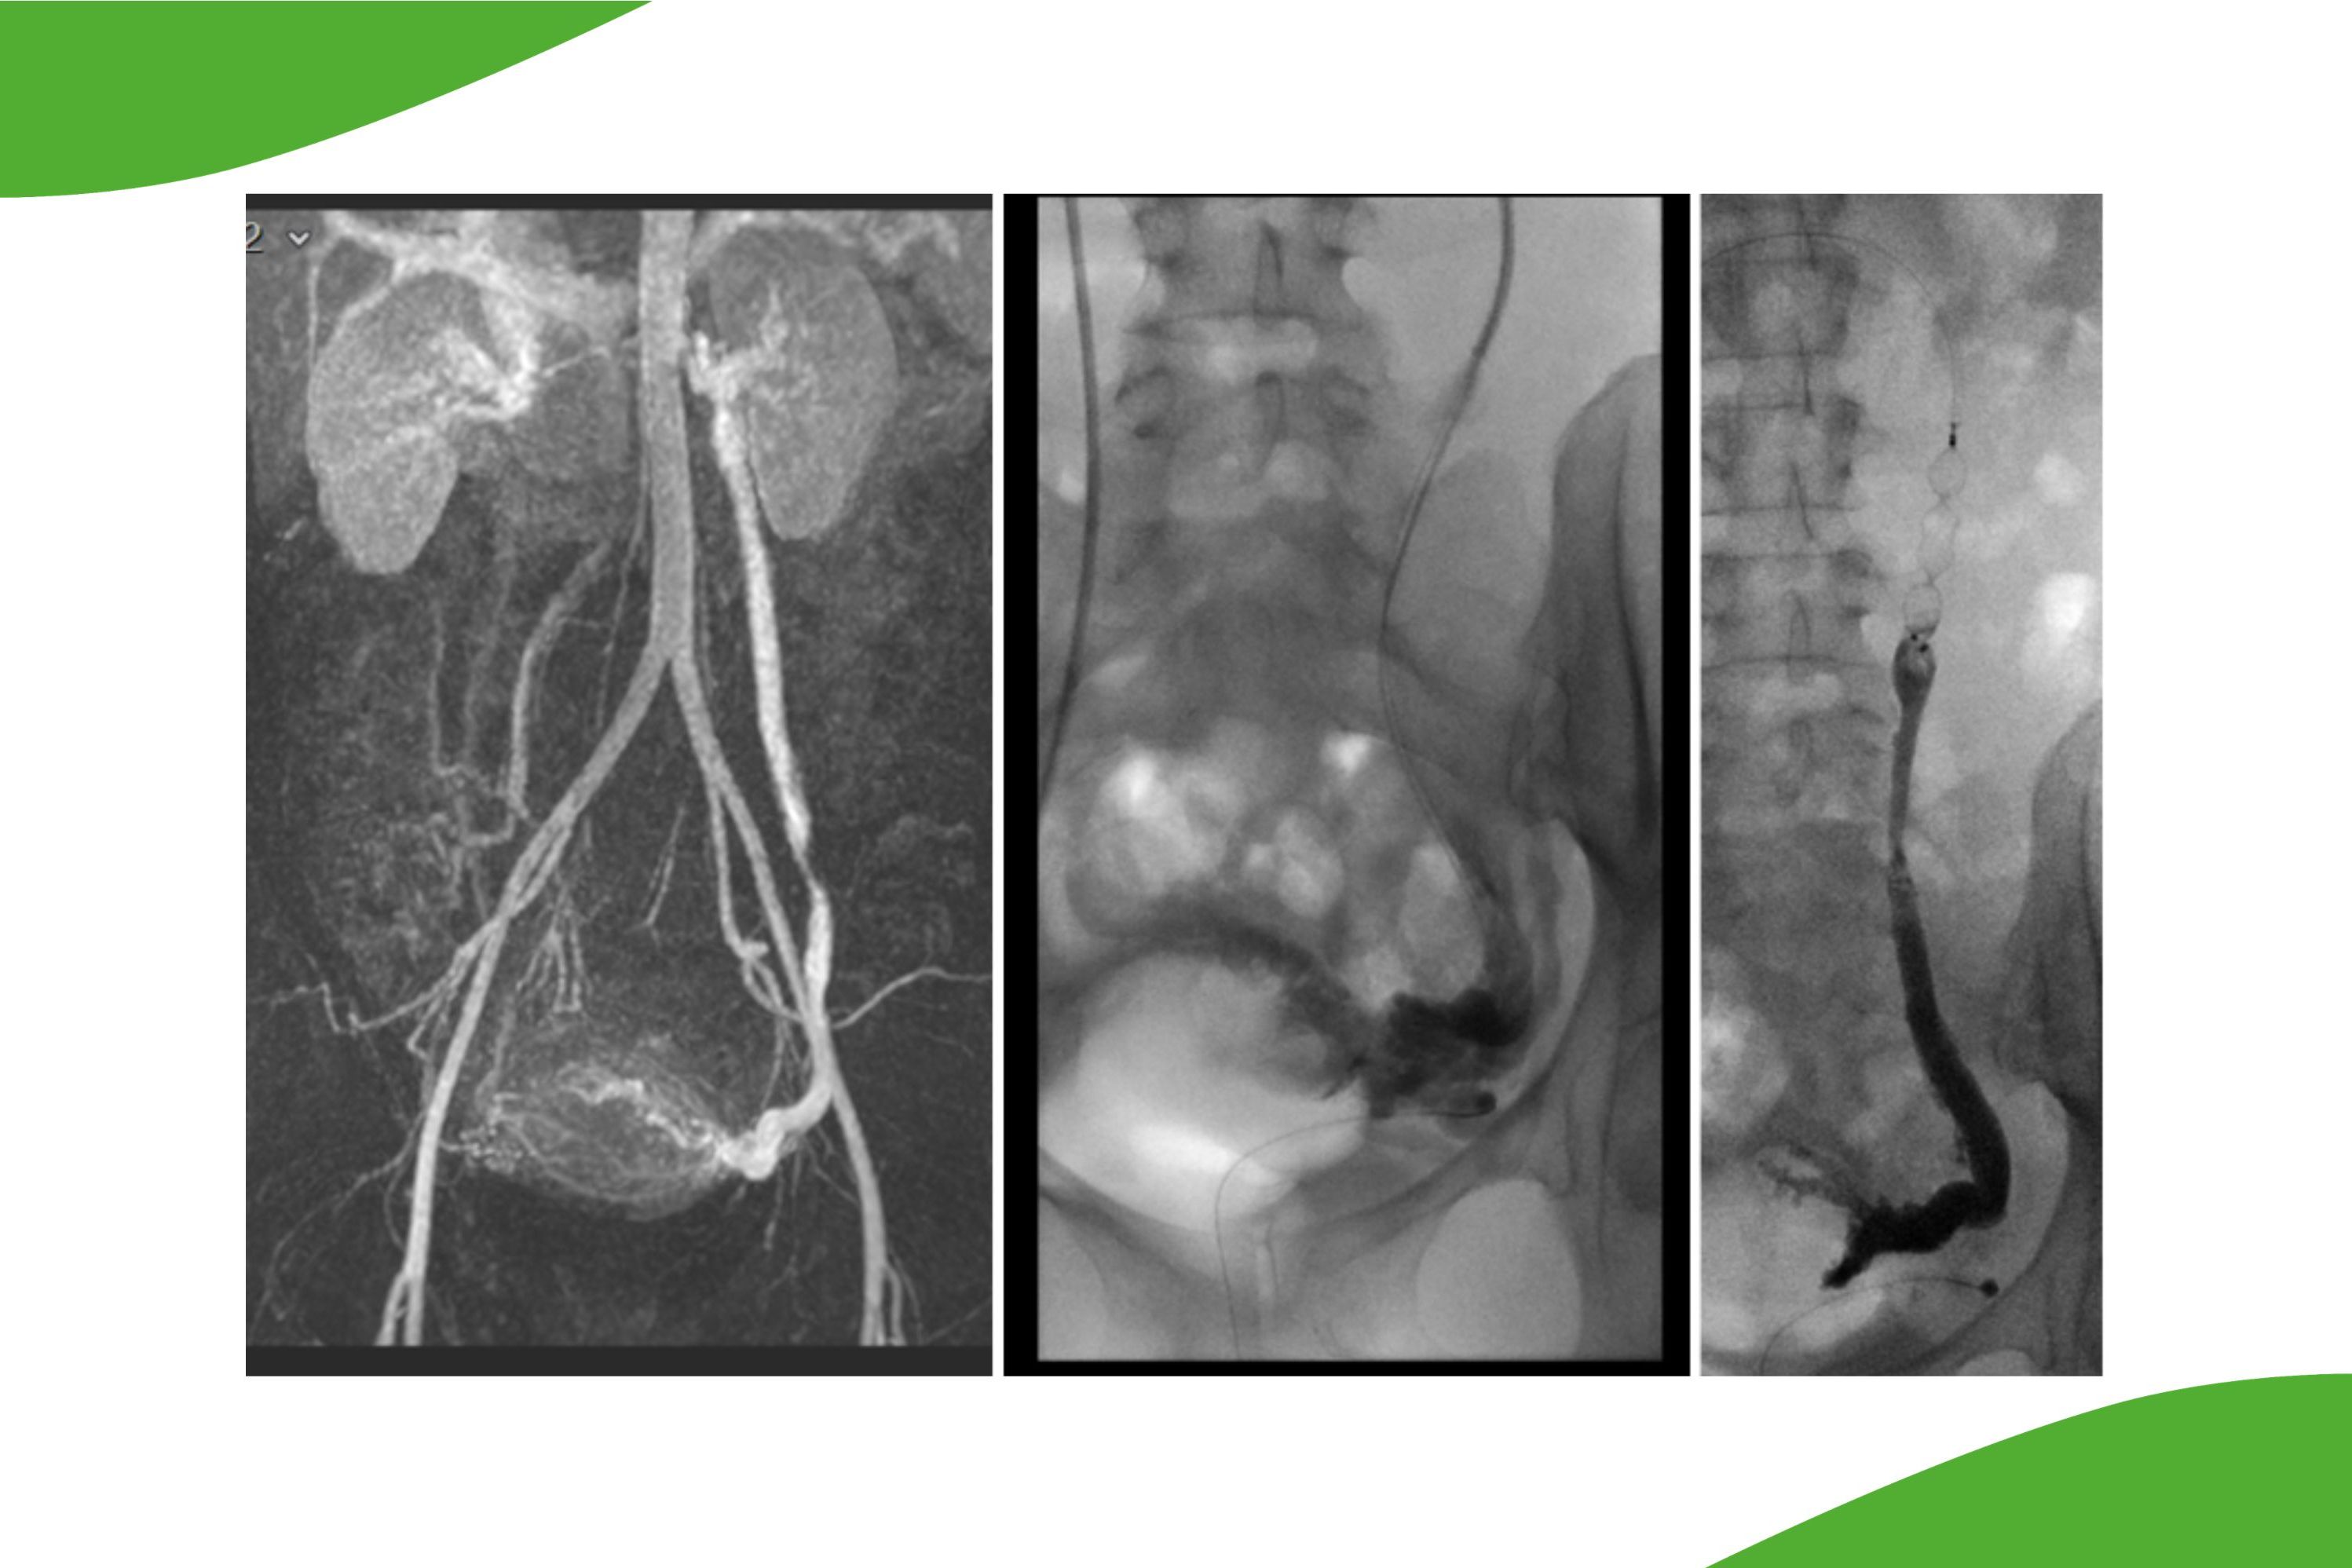

Rekanalisation eines alten Beckenvenenverschlusses bei posthrombotischem Syndrom. Links DSA-vor dem Eingriff, rechts wiedereröffnete Beckenvenen nach Stent-PTA.

Großer Embolus, gefangen in einem Cavafilter (Pfeil). Links: native, rechts: DSA-Aufnahme. Schrägeinstellung, um die Überlagerung mit dem Kolon zu vermeiden